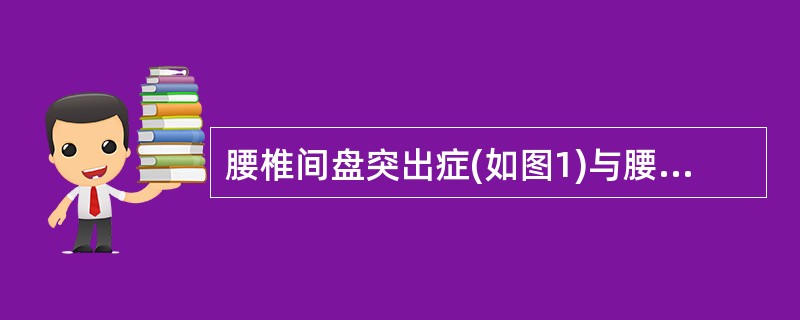

腰椎间盘突出症(如图1)与腰椎管狭窄症(如图2)临床症状的主要不同点为()